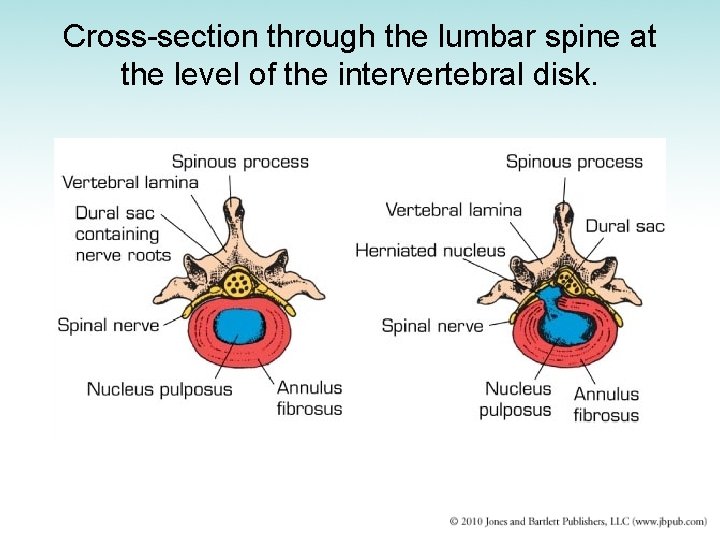

Cross-section through the lumbar spine at the level of the intervertebral disk.

Intervertebral Disk Disease • Intervertebral disks undergo progressive wear -and-tear degeneration of both nucleus and annulus • Nucleus pulposus may be extruded through tear in annulus fibrosus • Manifestation – Sudden onset of back pain radiating down the leg • Diagnosis: CT scan or myelogram • Treatment: surgery